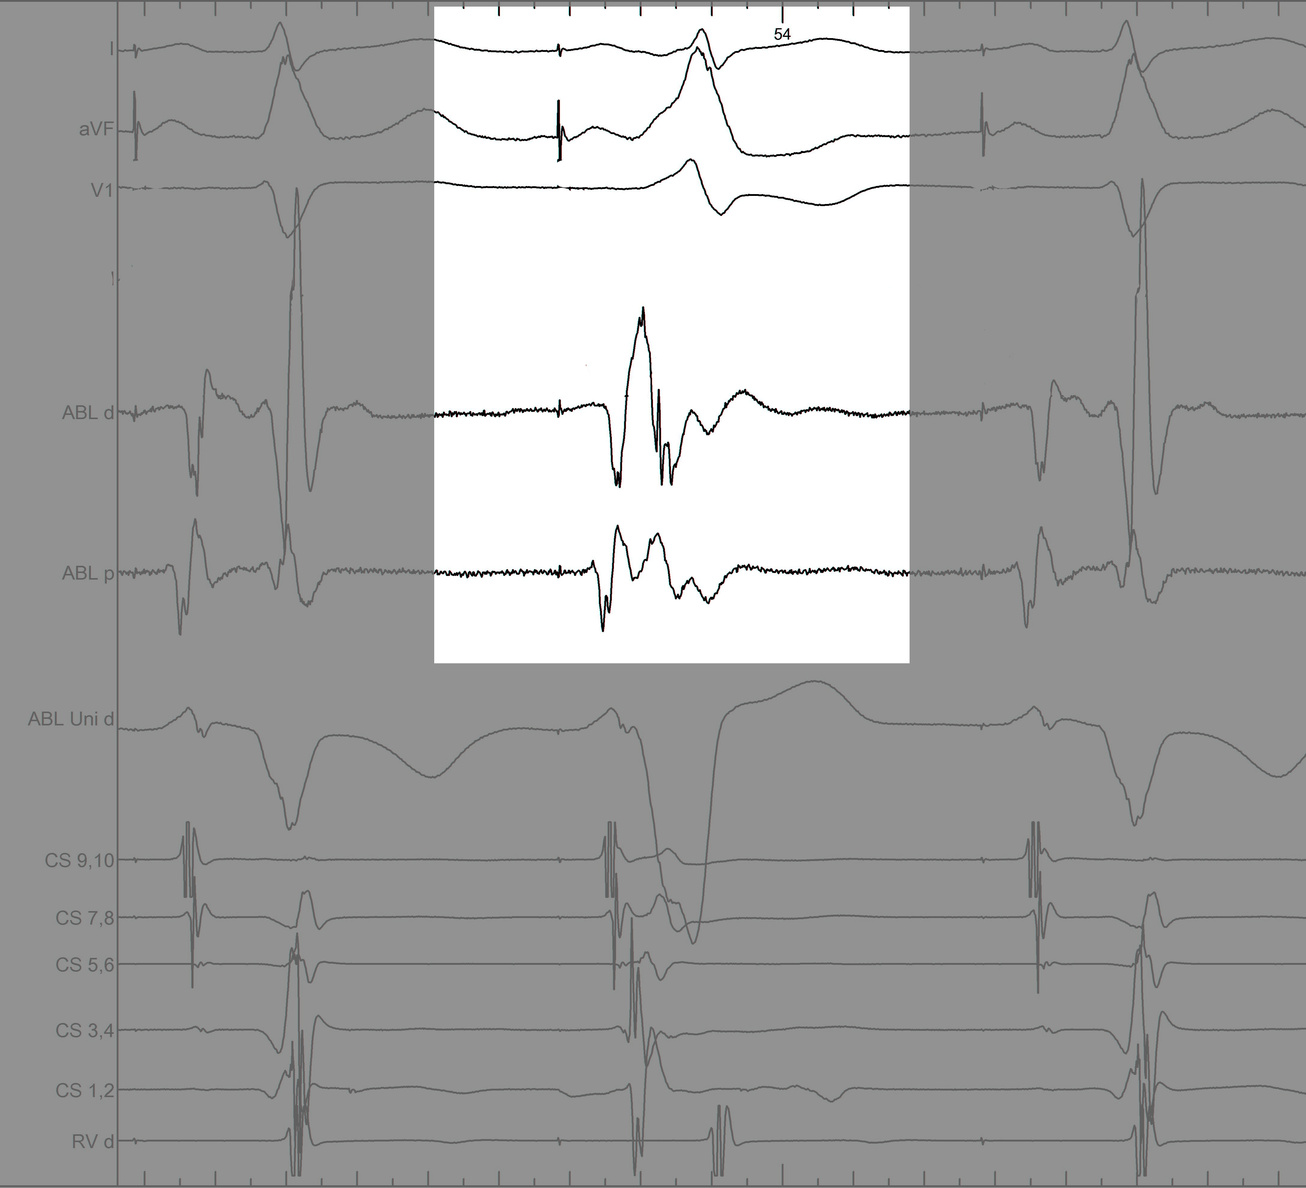

Use unipolar EGMs

uni.jpg

Identify components of the signal

mask1.jpg

mask2.jpg

mask3.jpg

mask4.jpg